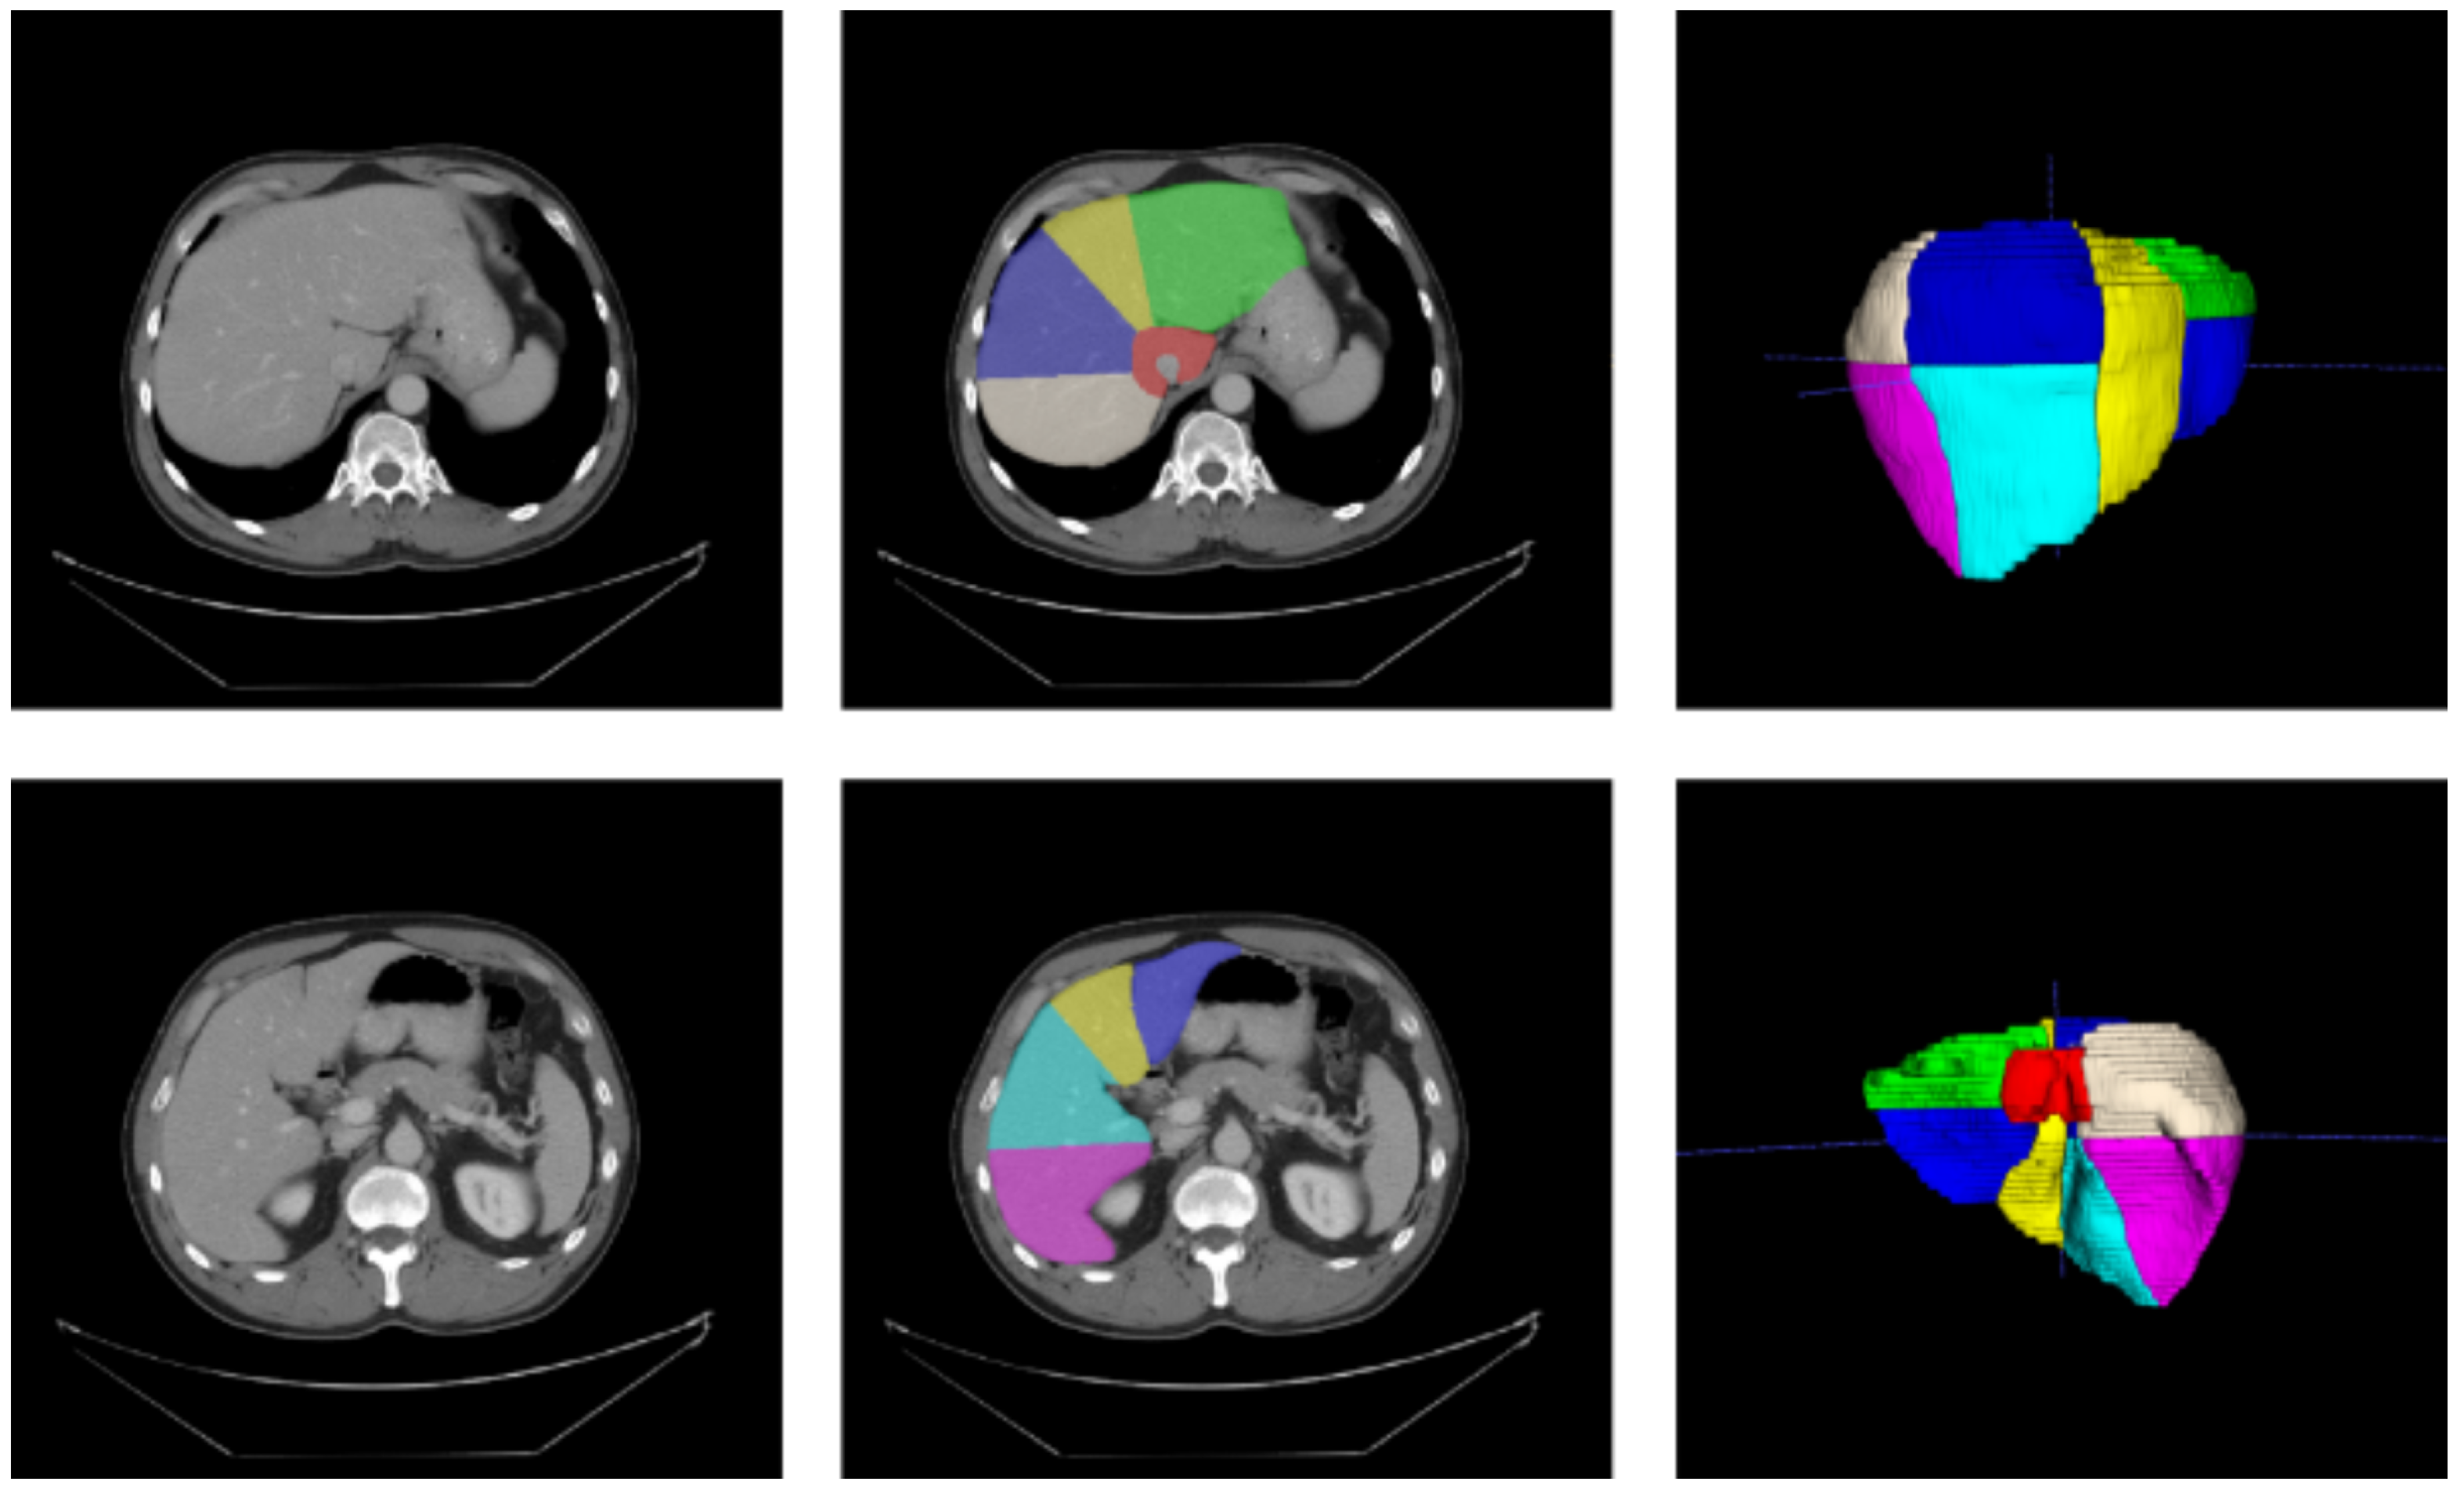

To train and validate our models, we used the Medical Segmentation Decathlon Task 08 (MSD 08 dataset [57]). This dataset is composed of 443 portal venous phase CT scans. The pixel spacing in the direction is in the range , whereas the thickness lies between . We considered liver segments’ annotations (n = 193) realized in a studio by Lenovo [21]. We exploited 168 CT scans as the training set and 25 CT scans as the validation set. For the selected training set, the frequencies of class values for each segment are represented in Table 1. Some examples from the MSD 08 dataset with the annotations of the Lenovo team are depicted in Figure 1. As pre-processing, images were clipped to the Hounsfield Unit (HU) range and then rescaled in the range , as already performed in [14].

Figure 1.

Medical Segmentation Decathlon Task 08 [57], with annotations from Tian et al. [21]. Left: original slices; middle: slices with segments’ annotations; right: meshes’ reconstructions of annotations.